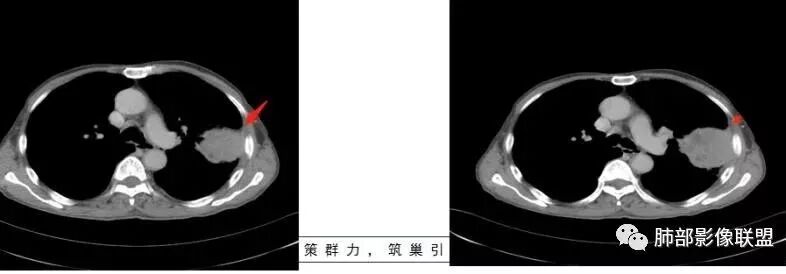

老年男性,外伤入院,“左上肺”实性肿块,边缘光滑,突破壁层胸膜并侵犯肋骨及肋间肌,增强扫描轻度强化,可见明显坏死。

• 胸CT:左肺上叶实性占位,病灶与支气管无关,病灶对斜裂挤压,病灶周围光滑,未见分叶、毛刺;纵隔窗可见病灶内低密度区,病灶对胸壁侵袭,并可见肋骨破坏。

胸CT:左上肺实性大肿块,边缘光滑,突破胸膜侵犯肋骨及肋间肌,纵隔淋巴结肿大,增强呈轻度强化,可见明显片状坏死。

胸部CT所见左肺上叶尖后段胸膜下较大山丘形肿块,边界清楚,宽基底与胸膜相贴,边缘与胸膜呈直角及锐角相交。邻近上叶尖后段支气管受压推挤,叶裂局部膨隆,病灶周围见少许磨玻璃密度影,边界不清。纵膈窗显示,肿块密度均匀,增强扫描呈不均匀轻度强化,邻近肋骨骨质破坏,病变沿肋间隙向外侵犯,局部胸膜增厚。纵膈内见多发小淋巴结,未见胸腔积液征象。综合考虑恶性占位,肉瘤样癌可能性大。腰椎及髋部考虑骨转移。

鳞癌,与吸烟关系密切,起源于支气管粘膜上皮,典型的征象就是支气管截断,周围型鳞癌往往体积较大,有时候与支气管关系不好判断,需要多平面重建看支气管的关系。

鳞癌因为侵袭性力较强,容易直接侵犯胸膜、胸壁,而周围型肺癌侵犯胸壁的90%癌肿是鳞癌,这也是鳞癌的一个特征性表现。邻近胸壁的脂肪层消失,胸壁肿块形成或有肋骨皮髓质边界不清的侵蚀破坏(而非边缘硬化或崩解)是瘤体向周围直接侵犯的可靠征象。

鳞癌因为破坏力强,其内可见灶样坏死区,坏死边界不清,其内血管破坏彻底。